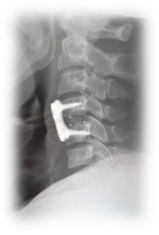

Male patient 36 years old had road traffic accident, with modified Frankel’s grade C and DFI stage 3. Skull traction was applied to restore of cervical alignment. Rapid anterior cervical approach, discectomy, unlocking of the facets, fusion with cervical cage and fixation with plate and screws (Figure 1).

Figure 1. Showing case 1 presentation. (a) Pre-operative plain X-ray (b) pre-operative skull traction (c) MRI cervical spine (d) post-operative anterior cervical cage fusion and plate fixation.